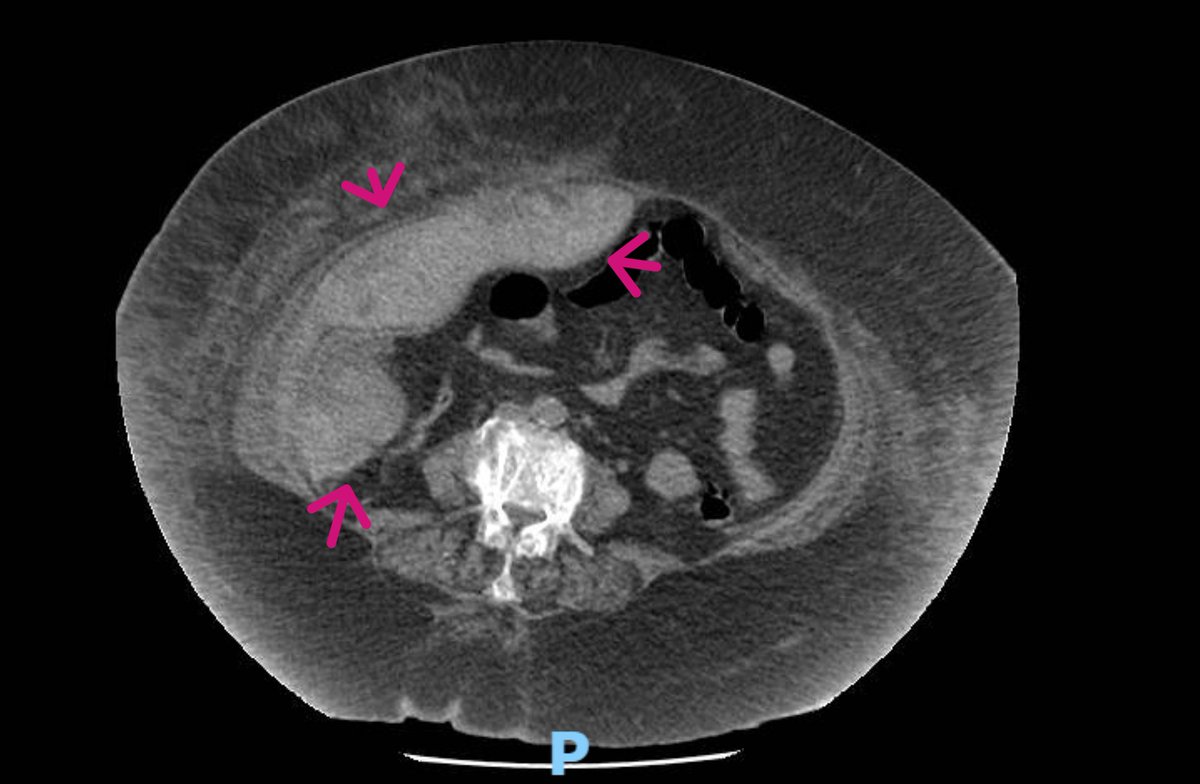

CT abd confirmed an intramuscular and intraperitoneal hematoma. Most probably related to dual antiplatelet and cough

muscular hematoma An 84-year-old with morbid obesity, type 2 resp failure, admitted with acute dropping of hemoglobin to 6 gm and right abdominal pain. POCUS showed right abd muscular huge hematoma